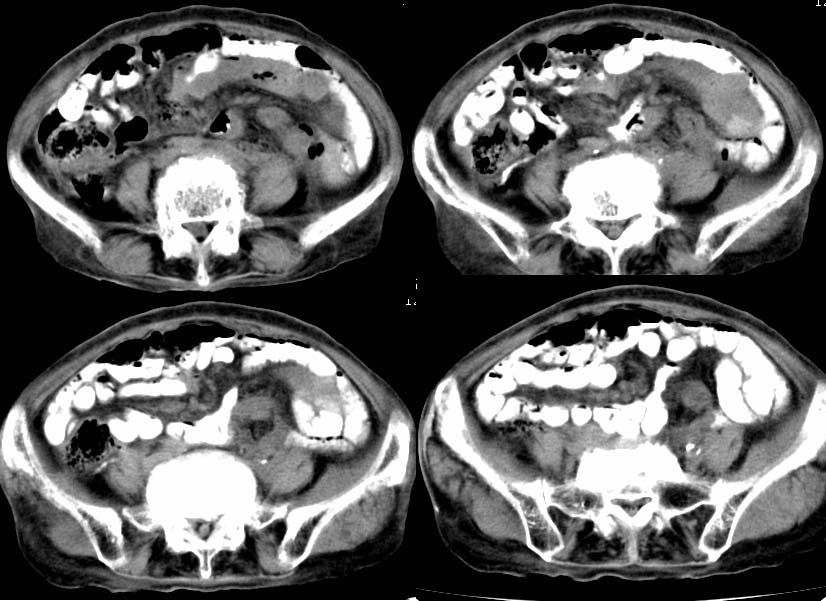

以下是引用zjzjr在2007-9-11 15:27:00的发言:[br]左侧小肠袢软组织影,其内有气体,新生物?建议胃肠造影。